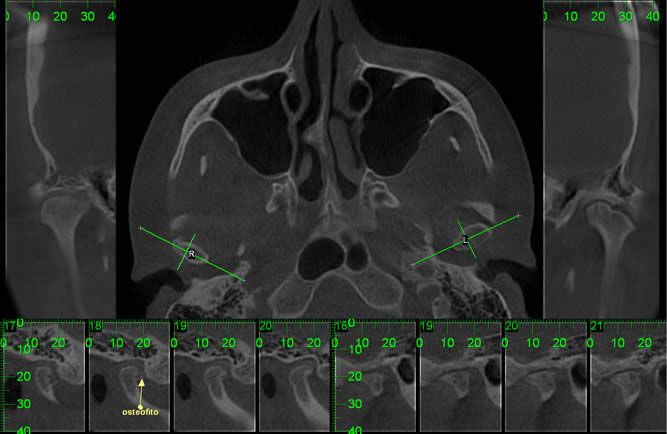

• ATM

Visualização dos componentes ósseos com a maior resolução existente na atualidade.

Paciente com assimetria, limitação de abertura bucal. Observa-se união óssea da porção posterior e lateral do côndilo ao esfeóide e zigomático.